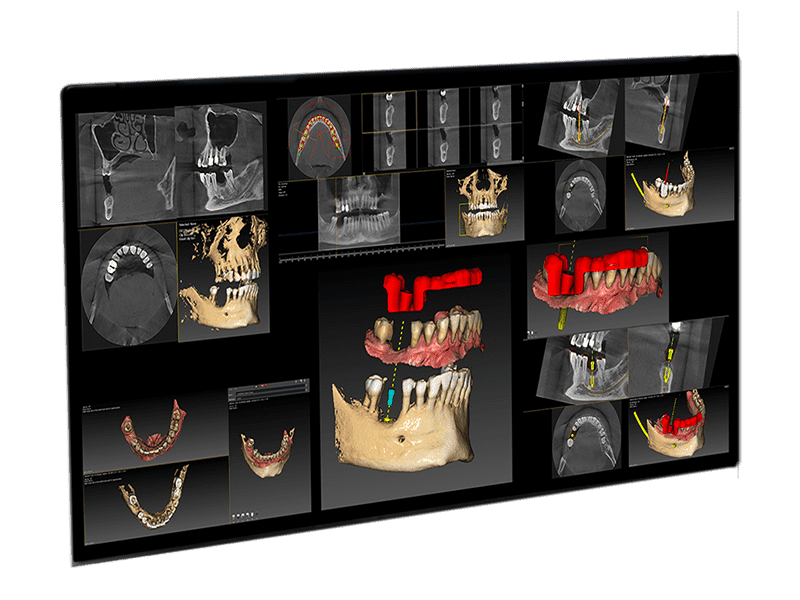

QuickVision 3D allows for simulating the placement of a dental implant on 2D and 3D models. To facilitate the surgical procedure, the patient’s main anatomical characteristics are identified.

This includes the precise location of the implant, potential collisions, and various other clinical aspects.

- Dental panoramic ray and Cone beam CT Prosthetic Project Planning

QuickVision 3D comes with all the core modules, enabling you to successfully complete your prosthetic project.

Quickvision 3D is a digital tool, allowing the preparation of guided implant surgery, but also the visualization and study of cone beam files.